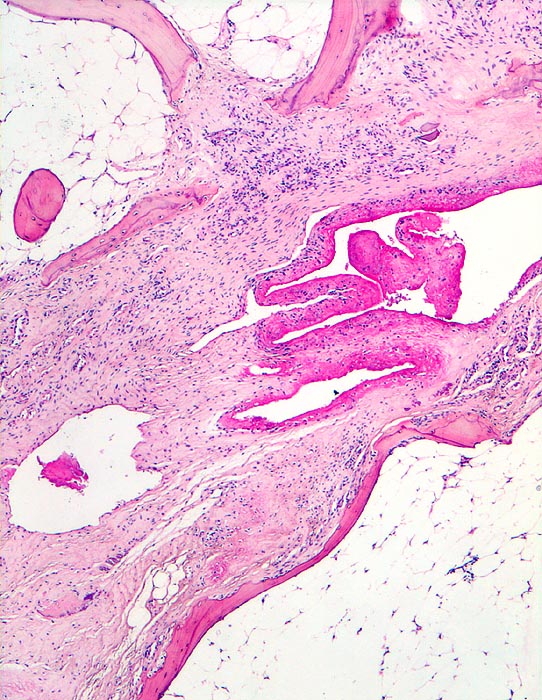

Rheumatoide Arthritis: Ankylose

Gelenk, Hand

Die Gelenkflächen sind durch bindegewebiges Pannusgewebe zerstört, welches den Gelenkknorpel resorbiert hat. Der Pannus überbrückt und fixiert den Gelenkspalt. Wenig Fibrinauflagerungen im Gelenkspalt.

Langjährige rheumatoide Arthritis mit Deformation der Fingergelenke und Ulnardeviation der Finger.